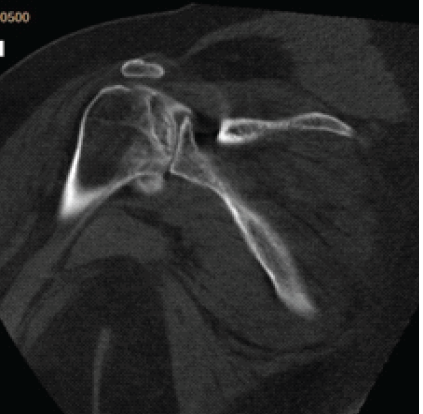

Modified Posterior Approach for Scapular Body Non-union: A Case Report

Deepak Kumar , Arjit Bansal , Sai Surya Dinesh Pydi , M Harshith , Kartik Sharma